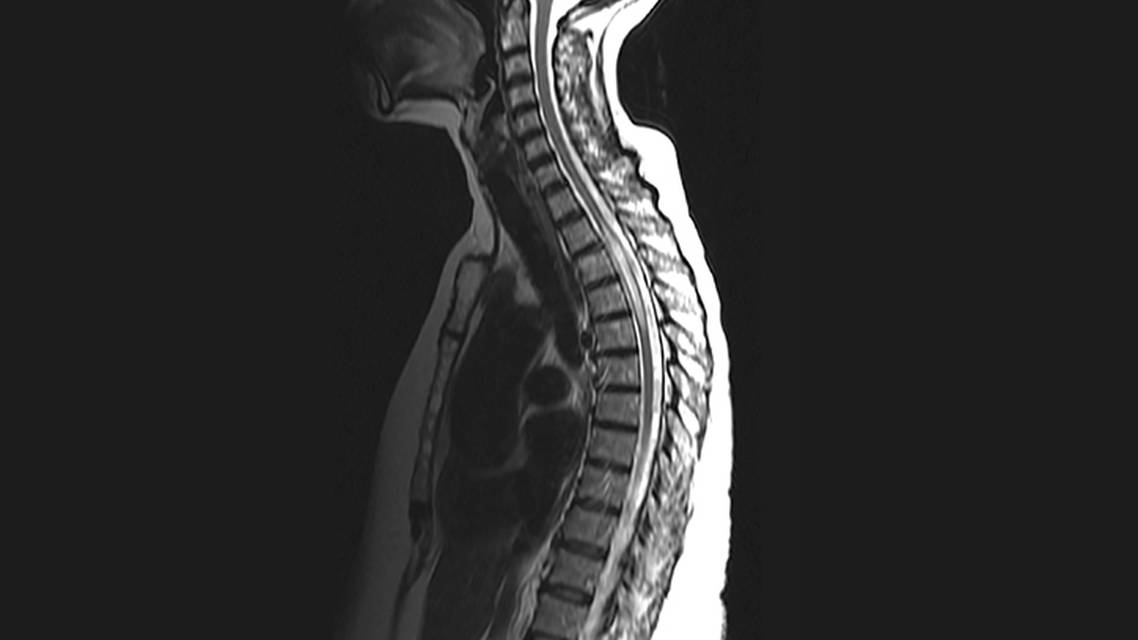

A right-handed African-American woman, age 61, presented with multiple comorbidities including a 22-year history of well-controlled systemic lupus erythematosus (SLE); rheumatoid arthritis, treated with chronic prednisone therapy; Sjögren’s syndrome; gout; low-grade mucosa-associated lymphoid tissue (MALT) lymphoma of left parotid gland status postresection; and hepatitis C. Ms. A came to the emergency department with acute onset of constrictive, band-like sensations around her chest associated with paresthesia and numbness in her trunk and bilateral lower extremities and subsequent development of urinary incontinence. On examination, she was found to have mild weakness of bilateral lower extremities, loss of sensation to all modalities below the T4 level, and sensory ataxia leading to an unsteady gait. Her visual acuity, color vision, and pupillary light reaction were intact bilaterally. Ms. A’s brain MRI had findings of mild patchy signal abnormalities in cerebral white matter that were consistent with small vessel ischemic changes. Cervical, thoracic, and lumbar spine MRI findings included an expansive T2 hyperintense signal measuring 5.8 cm from T2 to T5, consistent with longitudinally extensive transverse myelitis (LETM) (Figure). Postcontrast imaging findings of abnormal enhancement at the T3 to T4 level were present.